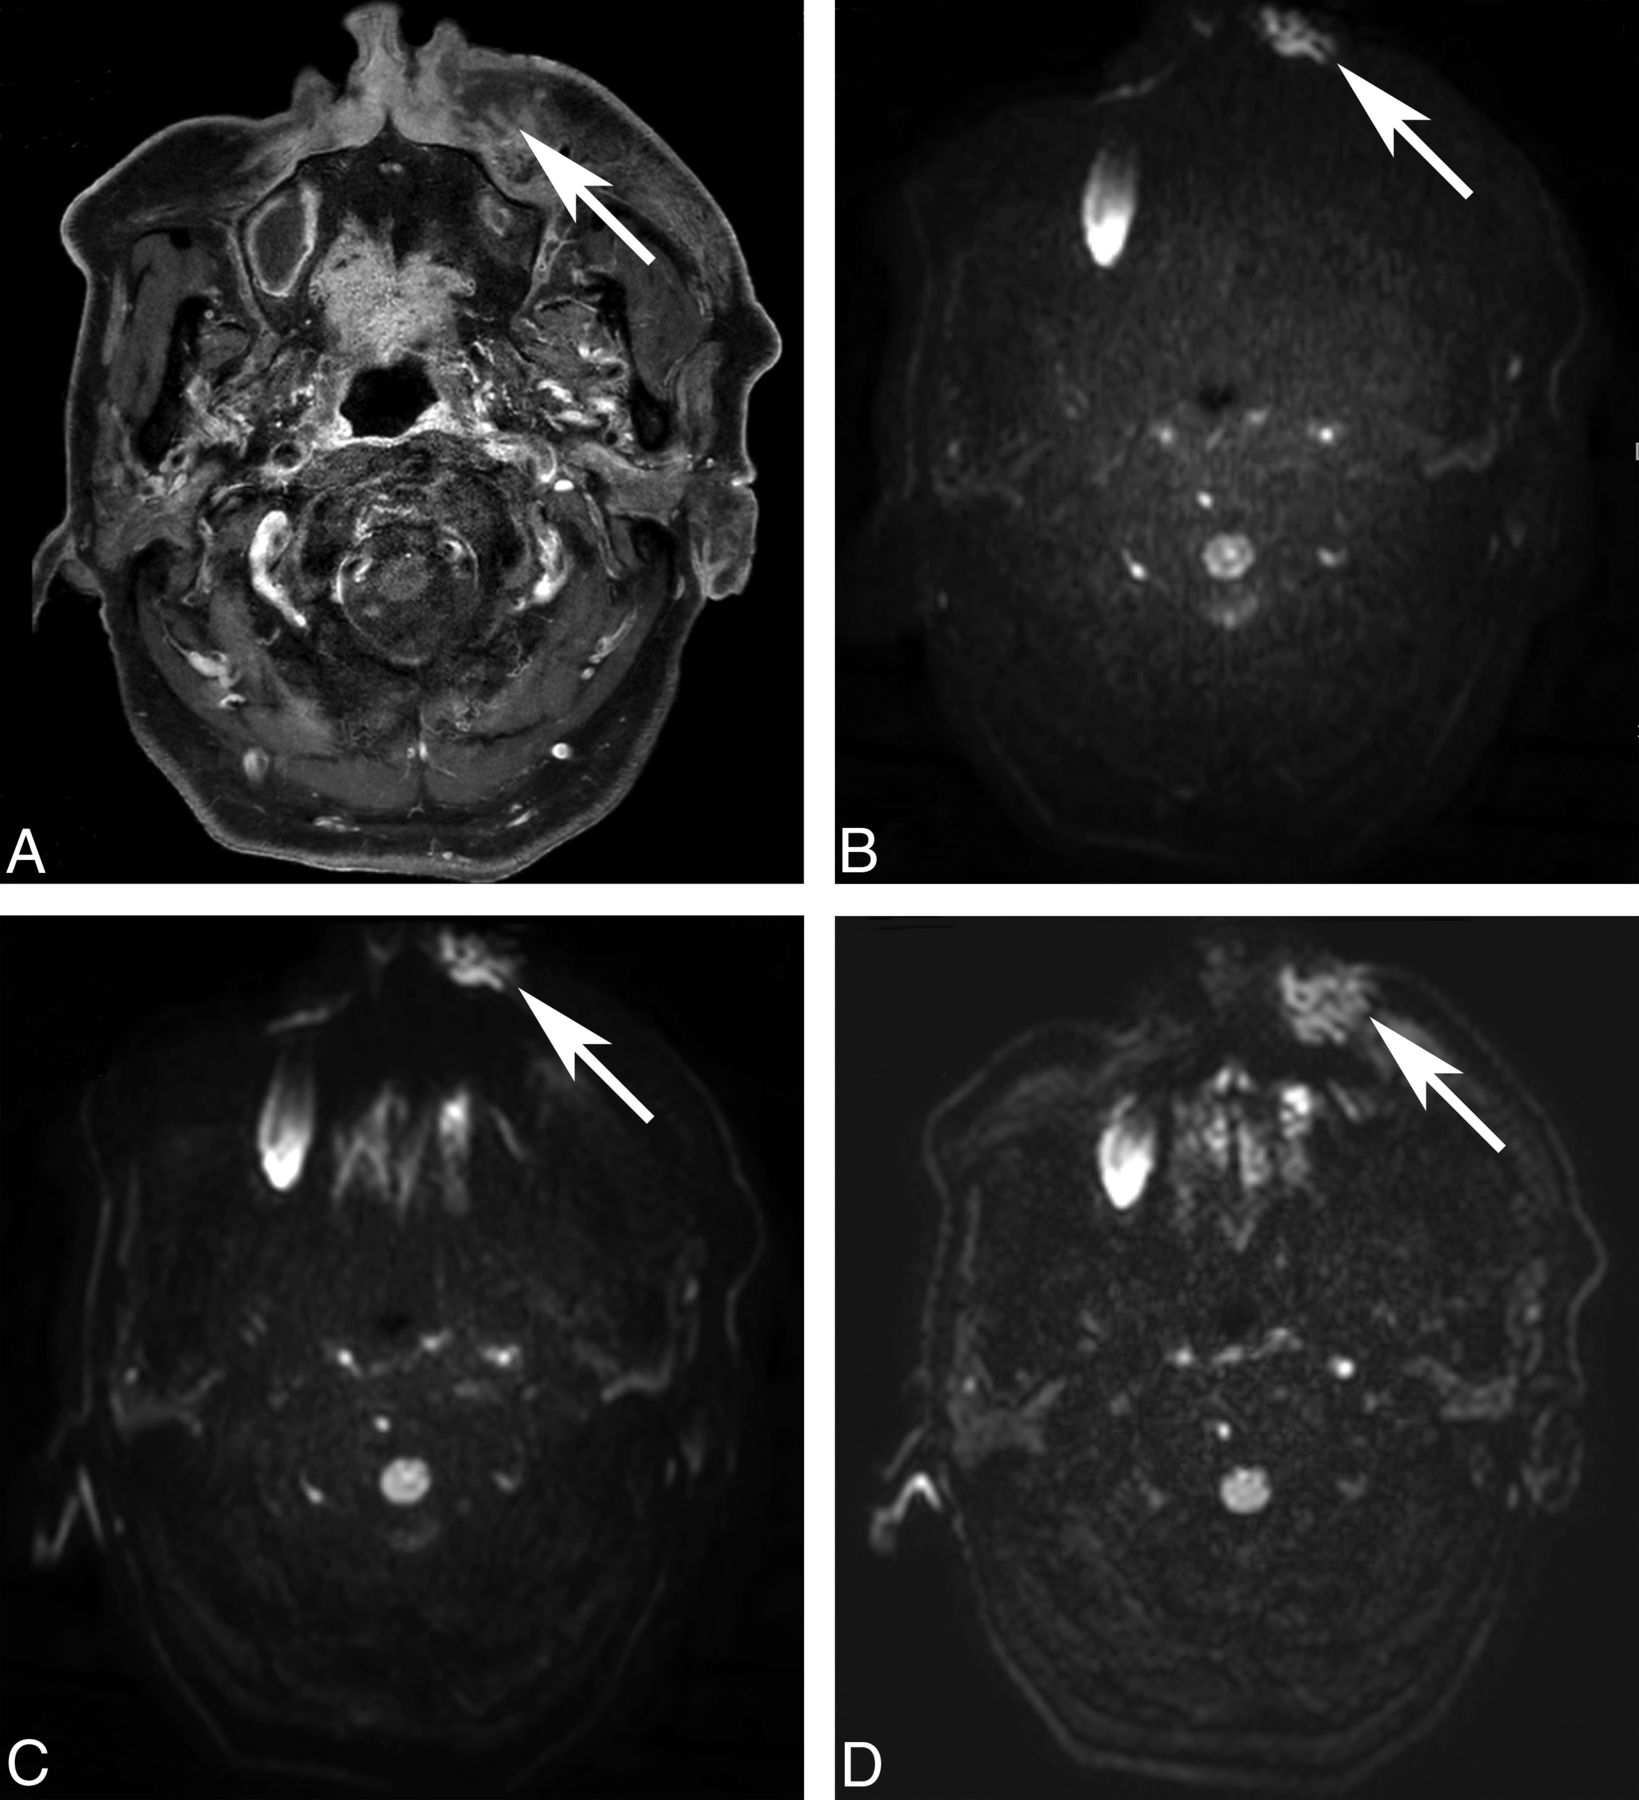

Fat-suppression uniformity of DWI. A 49-year-old man underwent MR imaging for staging of left maxillary sinus cancer (A, post-contrast-enhanced T1WI, arrow). On ssEPI-STIR (B), fat suppression is homogeneous without disrupting the original mass (arrow). On ssEPI-SPIR (C), unsuppressed fat signal (arrows) in the subcutaneous layer creates ghost artifacts that obscure the original mass, making the lesion assessment unfeasible. Unlike ssEPI-SPIR, unsuppressed fat signal (arrow) does not shift much to cover the mass on msEPI-SPIR (D).

Our results of the qualitative imaging assessment showed that fat suppression was more homogeneous in ssEPI-STIR than in msEPI-SPIR and ssEPI-SPIR (On-line Table 4). This result agrees with previous studies, which reported that STIR could provide more homogeneous fat suppression in body parts with severe field inhomogeneity than SPIR.4,10⇓–12,19 With the same use of SPIR, msEPI-SPIR had a higher visual score for fat-suppression uniformity than ssEPI-SPIR in the buccal and mental regions. We believe that this result was due to the reduction of ghost artifacts from unsuppressed fat signals on the msEPI sequence compared with the ssEPI sequence (Fig 1).5,15⇓–17 Unlike ssEPI-SPIR, the reduction of ghost artifacts could eliminate the obscuring of targeted structures by unsuppressed fat signals on msEPI-SPIR. The difference between msEPI-SPIR and ssEPI-SPIR was not significant in the orbital region and posterior neck where fat suppression was equally excellent and in the shoulder where both sequences failed in homogeneous fat suppression. In the orbital region, all 3 sequences showed comparably excellent fat-suppression homogeneity. More important, regarding image distortion, the distortion was much more reduced in msEPI-SPIR than in ssEPI-STIR and ssEPI-SPIR (On-line Table 5 and Fig 2). Taken together with the above results, we concluded through visual assessment that msEPI-SPIR provided the best image quality with relatively homogeneous fat suppression and less image distortion compared with ssEPI-STIR and ssEPI-SPIR, but for imaging the shoulder region, msEPI-SPIR could be more limited than ssEPI-STIR.